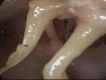

An overview of endoscopic ear surgery in 2018

Objective: To provide an overview of Endoscopic Ear Surgery, its development, principles, and penetration in otology practice in 2018.

Results: The number of publications on use of endoscope has increased from 6 in 1990 to an accumulated total of 451 in 2018. There has been a clear shift in the area of interest away from diagnostic endoscopy, to endoscope-assisted surgery, and lately, to transcanal endoscopic ear surgery (TEES). Survey results further documented the increased awareness of the value of the endoscope and its increased use in clinical practice.

Conclusion: TEES has gained traction as a subject of research interest and in clinical practice and has lately dominated the discussion on the use of endoscope in otology.